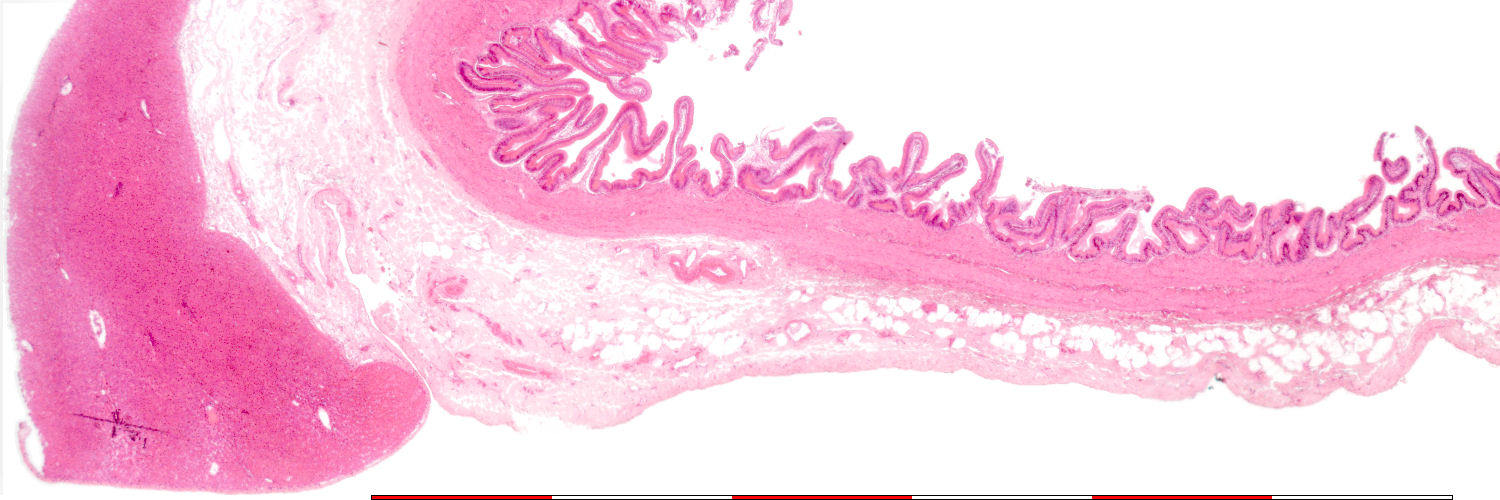

Low magnification of the gallbladder and liver

Liver

Mucosa

Muscularis externa

Adventitia

Serosa

Boundaries of layers